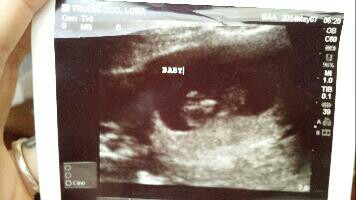

• That's not true. It's not always clesr. In fact identical twins are common to hide behind each othrr. Especially since her uterus is tilted and not at a normal positioning it's even more common for a twin to hide. I am pregnant with twins and we saw them really clear but then she couldn't find the one again...The next ultrasound could only see one. Then after that they were there again. Early ultrasounds do not always pick up twins. I don't know why mom's who saw THEIR babies think everyone has the same experience. Every mom should know there are rarely any rules to pregnancy! Here's a pic of my twins at 10wks